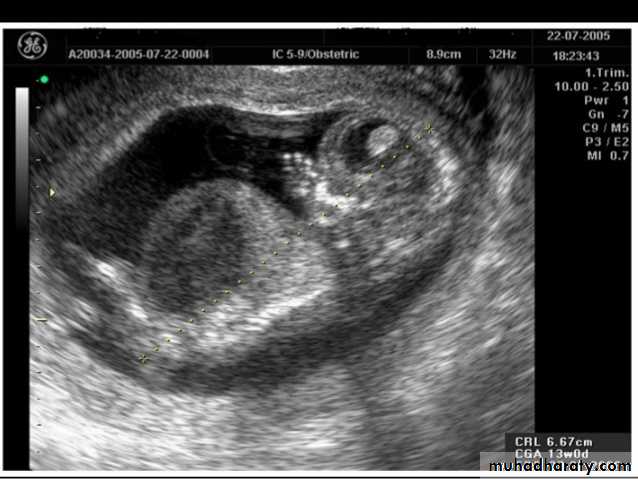

Blighted ovum

Anembryonic pregnancy is a form of a failed early pregnancy, where a gestational sac develops, but the embryo does not form. The term blighted ovum is synonymous with this, but is falling out of favour and is best avoided.

Radiographic features

Ultrasound

An anembryonic pregnancy may be diagnosed when there is no fetal pole identified on endovaginal scanning , and:

the size of the gestational sac is such that a fetal pole should be seen: MSD ≥25 mm on TVS (by RCOG criteria)